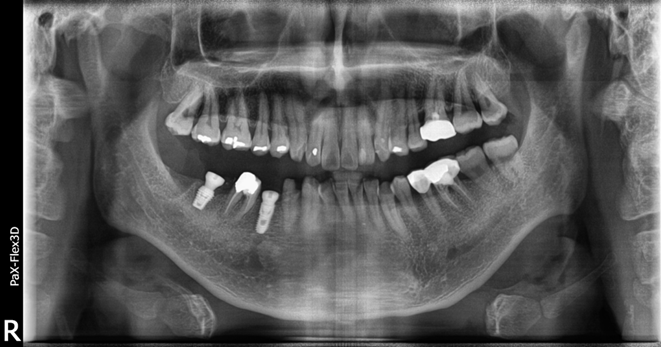

치아 머리 부분에 해당하는 보철물은 임플란트의 금속 픽스처가 뼈와 충분하게 유착되어 단단해질 때까지 기다렸다가

약 3개월 후인 지난 4월 말에 최종적으로 부착해 마무리 해드렸습니다.

환자분은 내원 당일 임플란트 식립이 가능했고, 뼈가 튼튼한 케이스라 임플란트가 잘 고정되어

내원 횟수를 최소화하고 치료 기간도 약 3개월 정도로 마무리할 수 있었습니다 ^^

환자분 역시 2개의 임플란트를 식립했음에도 불구하고 최종 보철물 완료까지 약 3개월 정도 소요되셔서 치료 기간을 단축할 수 있었습니다.